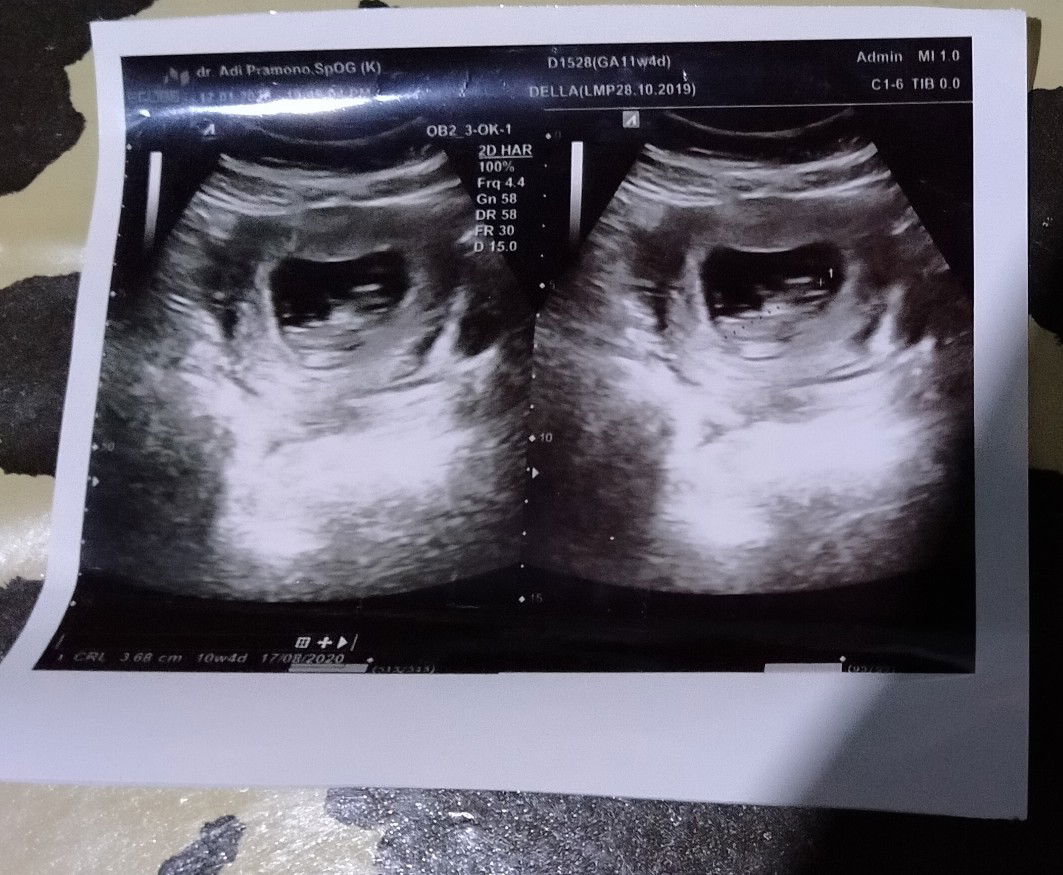

Malem bun Sy mau tnya kmrin sy cek usg ke dokter tapi sy masih bingung baca hasil usg nya Di tulisan GA 11w4d Sedangkan di CRLnya 3,68cm (10w4d) Itu maksudnya gimana ya bun Apa janin sy normal? Dan usia yg sebenernya yg mana ya bun?

GA itu perkiraan umur kehamilan bun CRL itu pnjang janin atau jarak dr ujg kpla k kaki Klau liat dr uk pnjg ny krg ssuai sm umur khmilan bun..dtmbh lg nutrisi ny.